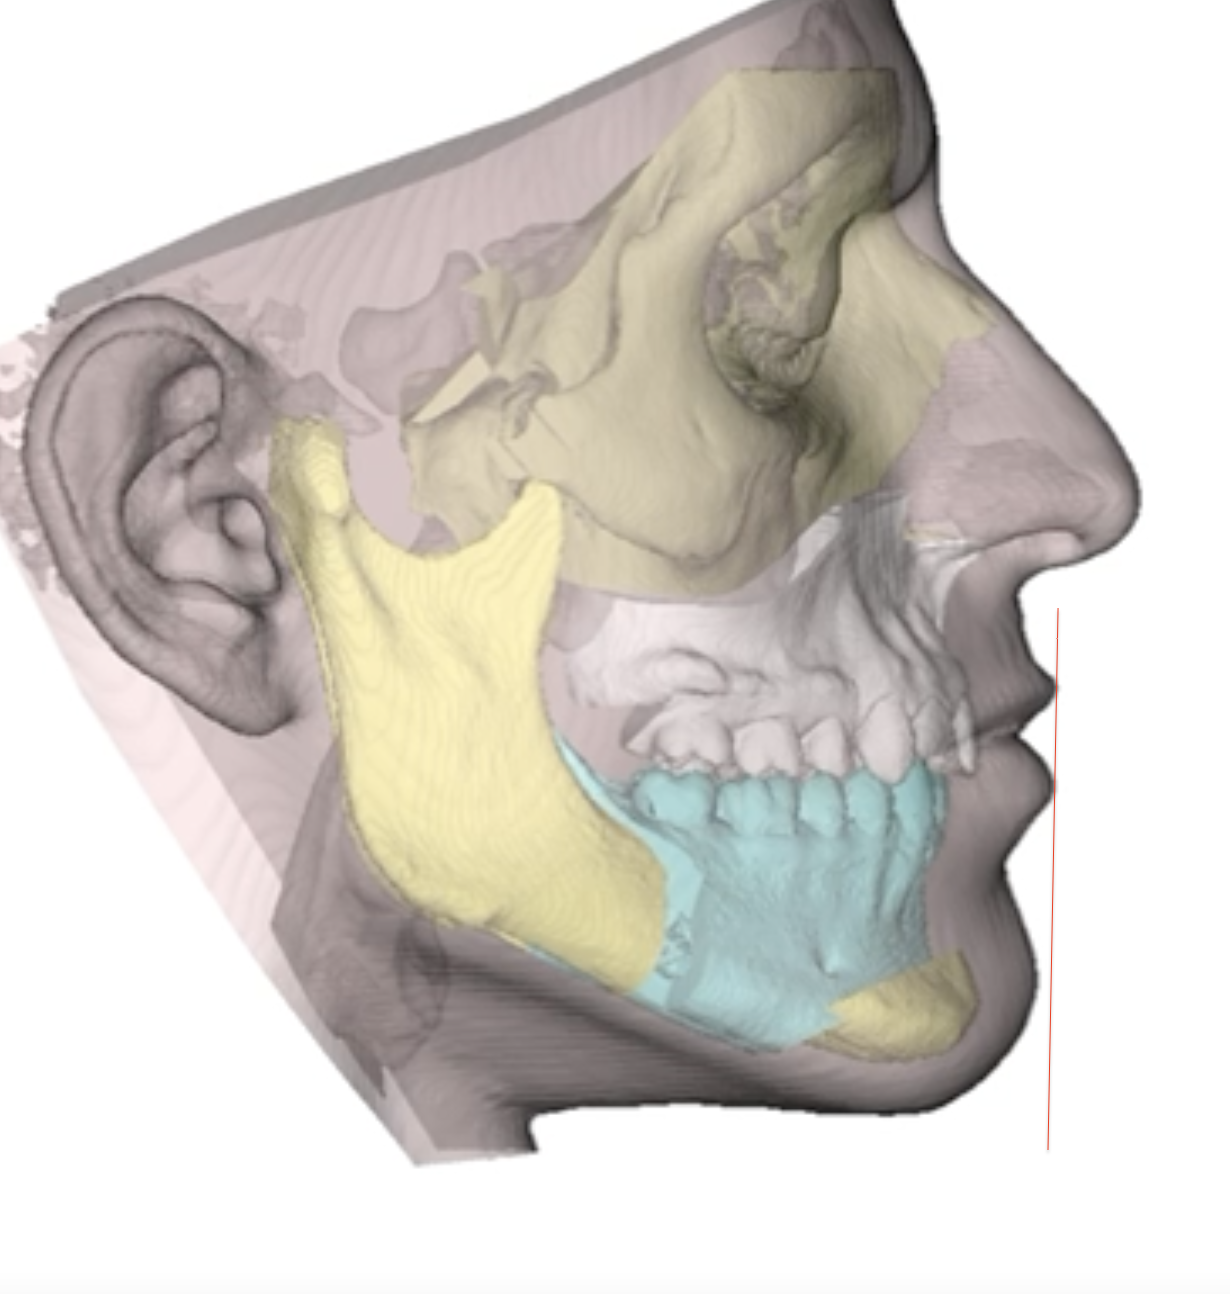

as you can see this is my final post op surgery positioning

my chin is behind the riedel line.

now the thing is how to fix it?

either i do more le forte 1 to make the upper lip ahead (6 mm instead of 5mm) which might give me a chimp lip

or i just do more genio to match the line

or maybe do you think i can fix my protrusive lower lip?

i am not sure what the correct move is to ensure good lip step and riedel line being good